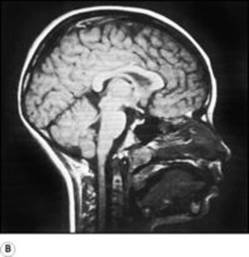

B9780702033957000079/f07-03a-9780702033957.jpg is missing

B9780702033957000079/f07-03b-9780702033957.jpg is missing

Figure 7.3

Brain and brainstem in sagittal section: A the medial surface of the left cerebral hemisphere, with the cerebellum and brainstem removed to expose the choroid fissure and the undersurface of the hemisphere; Bmagnetic resonance image of the head. Compare with A and note the corpus callosum, fornix, thalamus and interventricular foramen. The triangular fourth ventricle is seen between the cerebellum and the pons and medulla. The midbrain, with the superior and inferior colliculi on its posterior surface, is also seen.